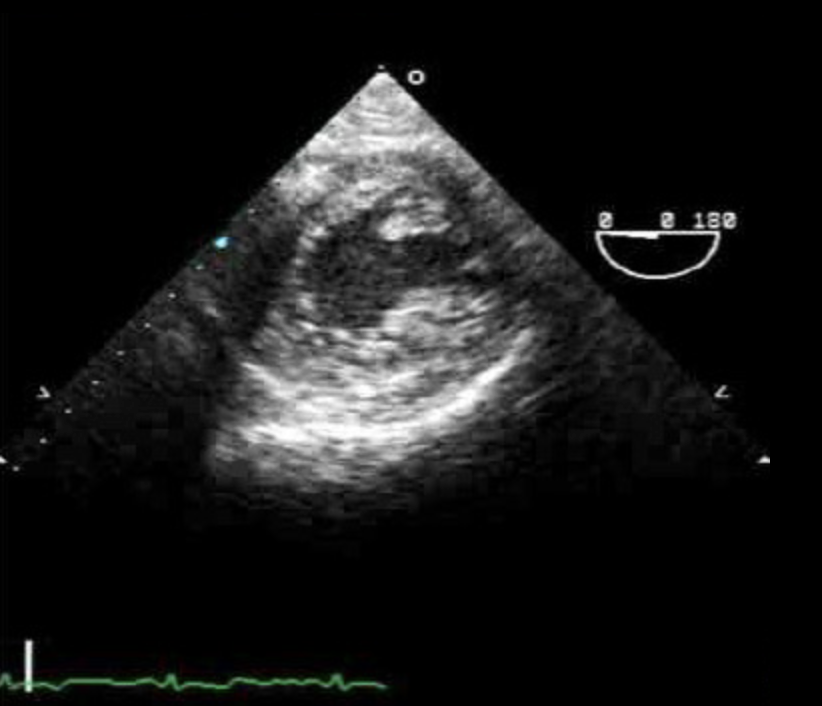

Transgastral Short Axis (TG SAX)

- In Magen einführen bis Magen/Leber sichtbar

- Anteflexion

- LV zentral durch Rotation links/rechts

- Zielstrukuren:

- Beide Papillarmuskeln

- Alle LV-Wandsegmente (inferior, anterior, septal, lateral)